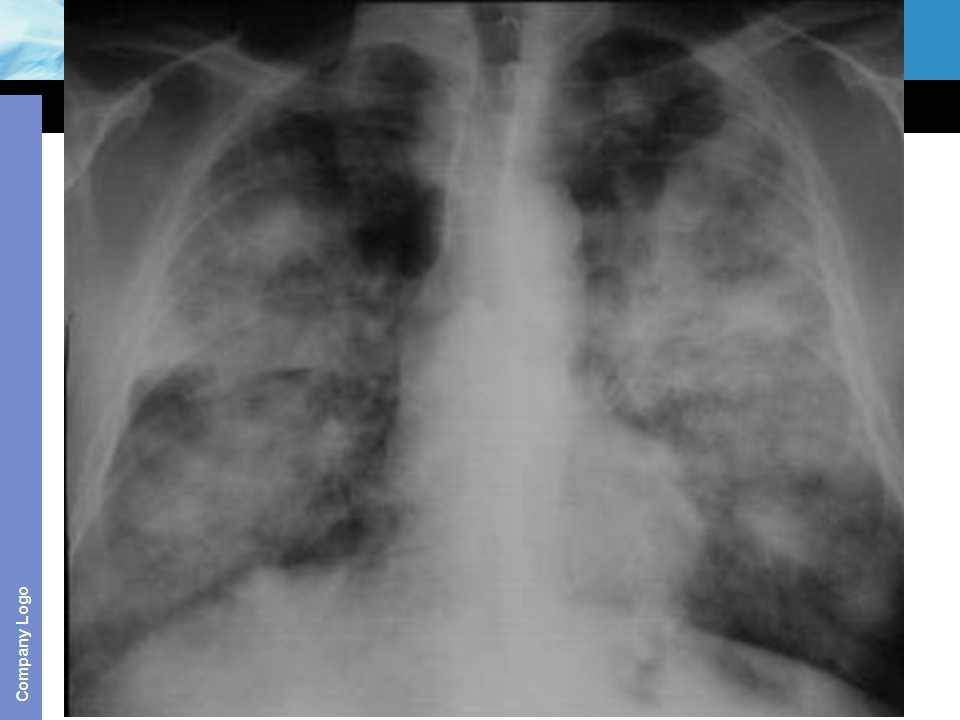

肺癌影像诊断